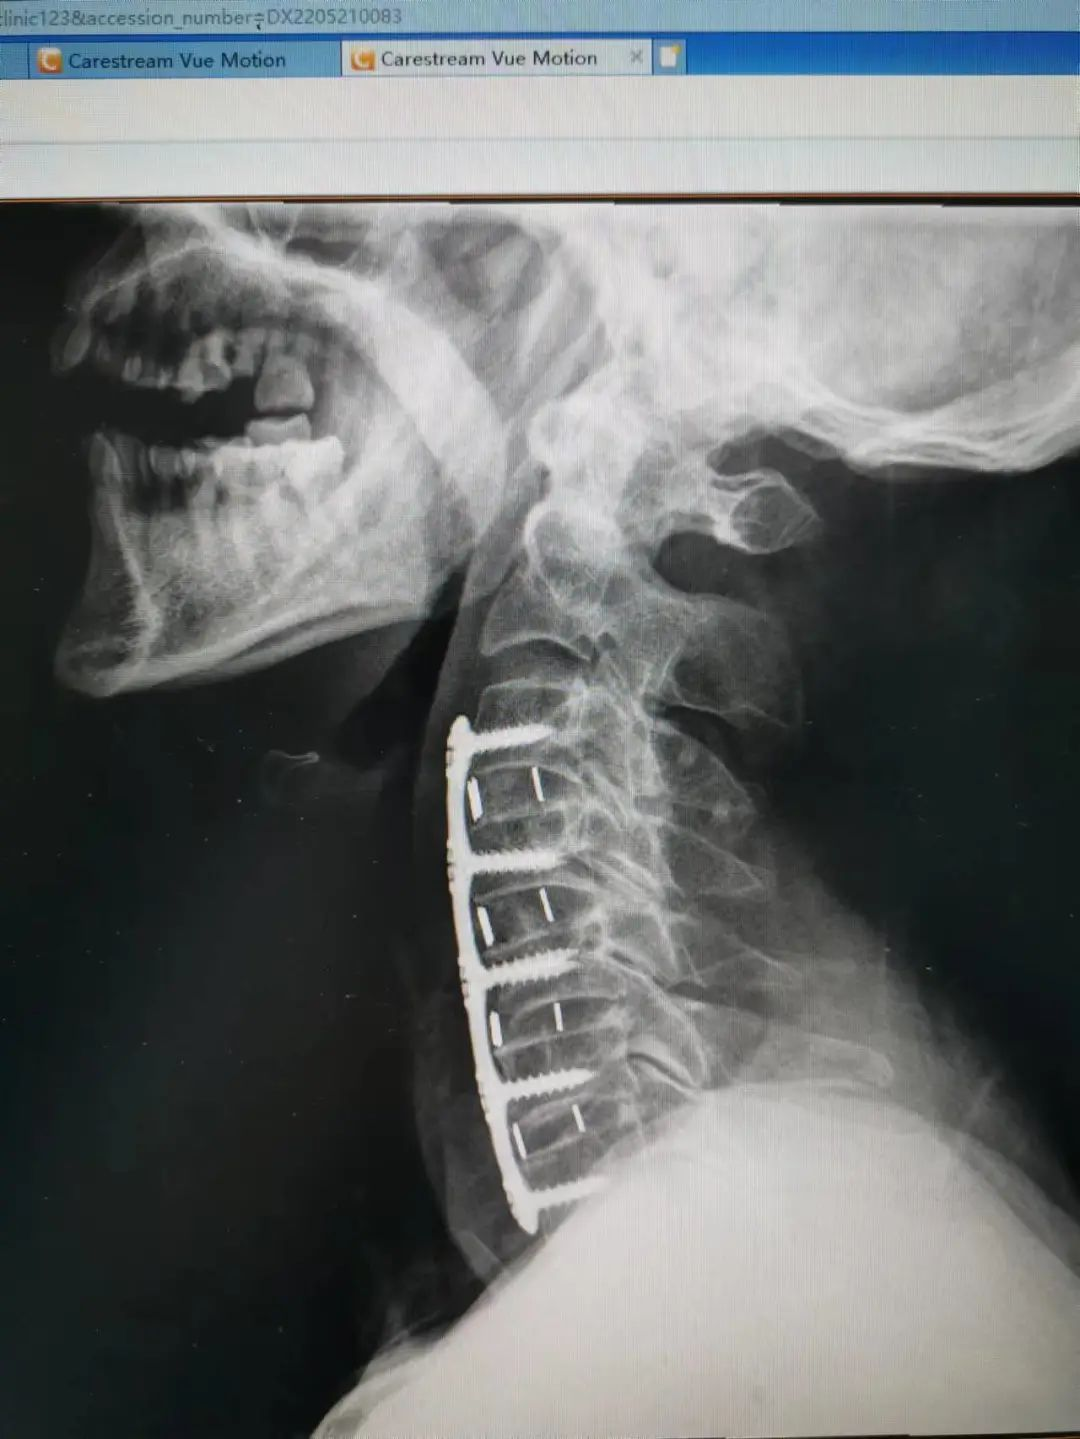

由于楊先生的病情嚴重,需住院治療。楊先生入院后,瀘州市中醫(yī)醫(yī)院骨傷二科科主任楊陳一制定了手術(shù)計劃,決定脊髓型頸椎病的手術(shù)從前路切開減壓,頸3/4 、頸4/5、 頸5/6、 頸6/7椎間盤切除,椎間融合,鋼板內(nèi)固定術(shù)手術(shù),而腰椎管狹窄癥經(jīng)后路切開減壓,腰3/4、腰4/5椎同盤動除,椎間融合、釘棒系統(tǒng)內(nèi)固定術(shù)。

楊先生術(shù)后拍片